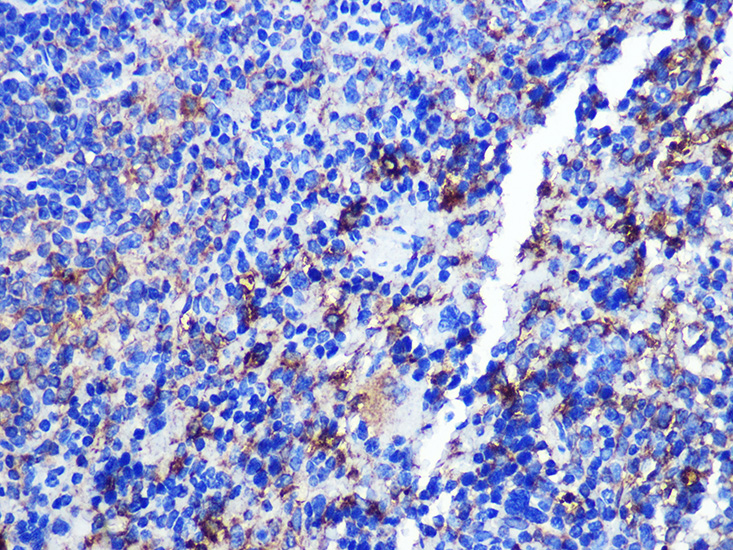

Immunohistochemistry of paraffin-embedded Mouse spleen using CD68 at dilution of 1:100 (40x lens).